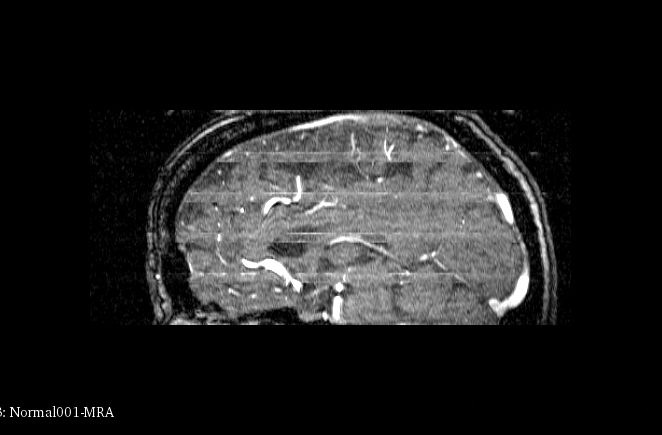

4、血管提取效果

如图所示的第一个图像展示了原始MRA扫描结果(Magnetic Resonance Angiography),其中在颅内可见一束明显的血管结构;第二个图像基于Hessian矩阵处理后得到血管区域分布;通过观察各幅图像效果可以看出该方法在血管定位方面表现较为准确;整体显示良好